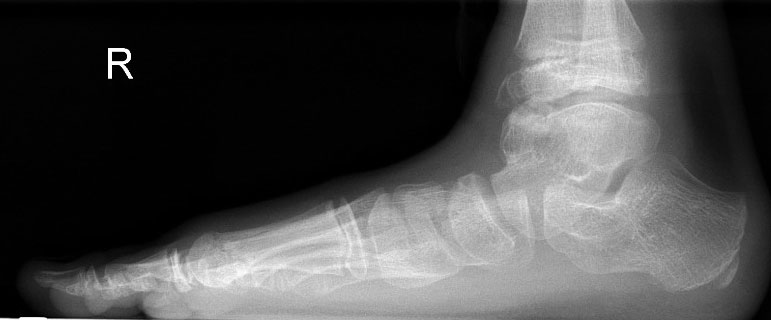

Konventionelle Röntgenaufnahmen bleiben in der bildgebenden Diagnostik von Knochen­tumoren das wichtigste diagnostische Werkzeug. Zahlreiche Informationen können hierdurch einfach, kostengünstig und im Vergleich zu einigen alternativen Untersuchungsmethoden strahlungsarm eingeholt werden. Die in der konventionellen Diagnostik eruierbaren und zur weiteren Abklärung erforderlichen Informationen beinhalten Befunde zu Topographie der Läsion (Lokalisation im Fußskelett und im individuellen Knochenbereich), Begrenzungen der Knochenläsion, Art der Osteodestruktion und Periostreaktion, radiologische Erscheinung der Tumormatrix (Zusammensetzung des Tumorgewebes, z.B. dystrophe Verkalkungen) sowie Verhalten und Ausmaß der Weichteilbeteiligung. Dabei sollte der abzubildende Knochen immer einschließlich der benachbarten Strukturen und angrenzenden Gelenke dargestellt werden. Die Röntgenaufnahmen sind stets in mind. zwei Ebenen anzufertigen. In Abhängig­keit der Beschwerden sind belastete Aufnahmen im Stehen anzustreben um zusätzliche Aussagen zur Statik zu erlangen. Die Schrägaufnahme des Fußes stellt eine sinnvolle Ergänzung zu den Standardeinstellungen (dorsoplantar/a.p. und streng lateral) dar um die Knochen des Fußskeletts möglichst überlagerungsfrei darstellen zu können. Ziel- und Spezialaufnahmen können bei Bedarf zusätzlich durchgeführt werden.

Nach Lodwick können die auf dem konventionellen Röntgenbild sichtbaren Destruktions­muster in drei Hauptgruppen unterteilt werden: Rein geographische (umschriebene) Knochendestruktion, die eine langsame Wachs­tums­geschwindigkeit widerspiegelt (Grad 1), gemischt geographisch/ mottenfraßartige Knochendestruktion mit permeativer Komponente, die eine intermediäre bis hohe Wachstums­geschwindigkeit anzeigt (Grad 2) und rein mottenfraßartige oder permeative Destruktion, die Zeichen einer sehr schnellen Wachstums­geschwindigkeit ist (Grad 3). Die erste Hauptgruppe unterteilt sich wiederum in sklerotisch deutlich abgrenzbare Läsionen (1a, sehr langsam wachsend), Osteolysen meist ohne Sklerosesaum und >1cm (1b, langsam wachsend) und weiterhin geographisch, also ausreichend gut abgrenzbare Osteolysen, welche obligat eine vollständige Kompaktapene­tration aufweisen (1c, mittlere Wachstumsgeschwindigkeit) (Tab. 1, Abb. 7). Sobald eine Grad 1c Knochenläsion nach Lodwick vorliegt, müssen weitere diagnostische Schritte diskutiert werden. Diese beinhalten üblicherweise eine MR-tomographische Untersuchung, gefolgt von einer Biopsie.

Die juvenile Knochenzyste (Syn. Solitäre Knochenzyste) findet sich am Fuß fast ausschließlich am Calcaneus im Bereich des Ward´schen Dreieckes bzw. im ventralen triangulären Bereich zwischen den Haupttrabekelgruppen (Diard´s Area 6) 3536. Eine physiologische Rarefi­zierung der Trabekelstrukturen in diesem Bereich muss strikt von tumorösen Raumforde­rungen differenziert werden 3738. Die Hauptindikation einer operativen Therapie stellen Schmerzen und eine drohende pathologische Fraktur dar (Abb. 23). Calcaneuszysten, die in der Koronarebene 100% des Querschnitts erreichen oder 30% der Sagittalebene einneh­men, gelten als potentiell frakturgefährdet und sollten auch bei Symptomfreiheit prophylak­tisch operiert werden 3940 (Abb. 24). Da simple Knochenzysten nicht selten als radiolo­gischer Zufallsbefund auffallen, kann auch die Tumorangst des Patienten eine Indikation darstellen. Eine differenzierte Aufklärung des betroffenen Patienten (und seiner Eltern) ist hier umso mehr erforderlich.